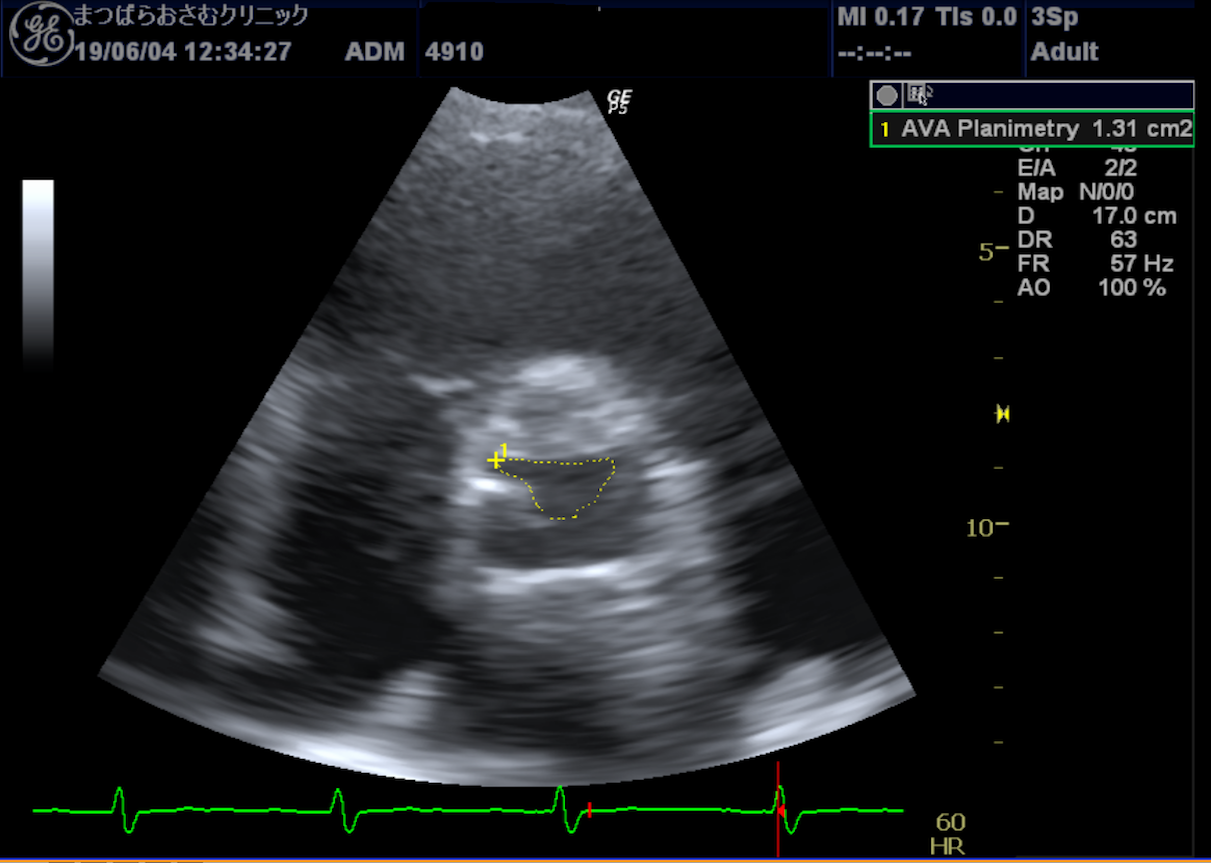

心エコー 心臓の動きや構造を観察する検査です。

胸にプローブ(探触子)を当てるだけで、心臓の大きさ、動き、弁の状態、血流の様子などをリアルタイムで確認できます。